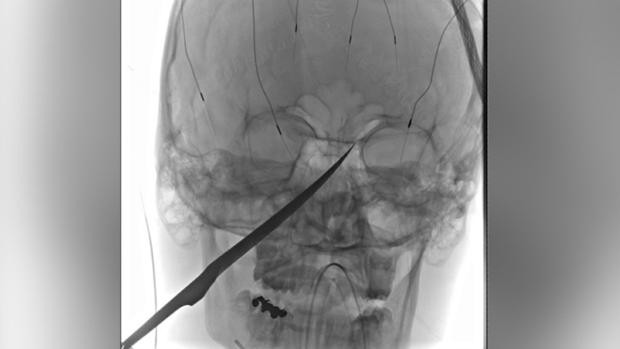

Comenzaron a jugar con él y, en un momento dado, el adolescente intentó quitar el arma a los más pequeños, por precaución; sin embargo, durante el forcejeo, el joven cayó al suelo y se clavó el cuchillo, perforándole la cara. Además, como explica en Facebook el hospital de la Universidad de Kansas, "la punta de la hoja estaba presionando su arteria carótida".

El cuchillo, de unos 25 centímetros, estaba incrustado en su cráneo. Sin embargo, la prioridad del equipo médico, encabezado por el cirujano Koji Ebersole, era la presión en las carótidas, una serie de ramas de la arteria aorta que nacen a corta distancia del corazón y, a través del cuello, suponen el principal suministro de sangre al cerebro.